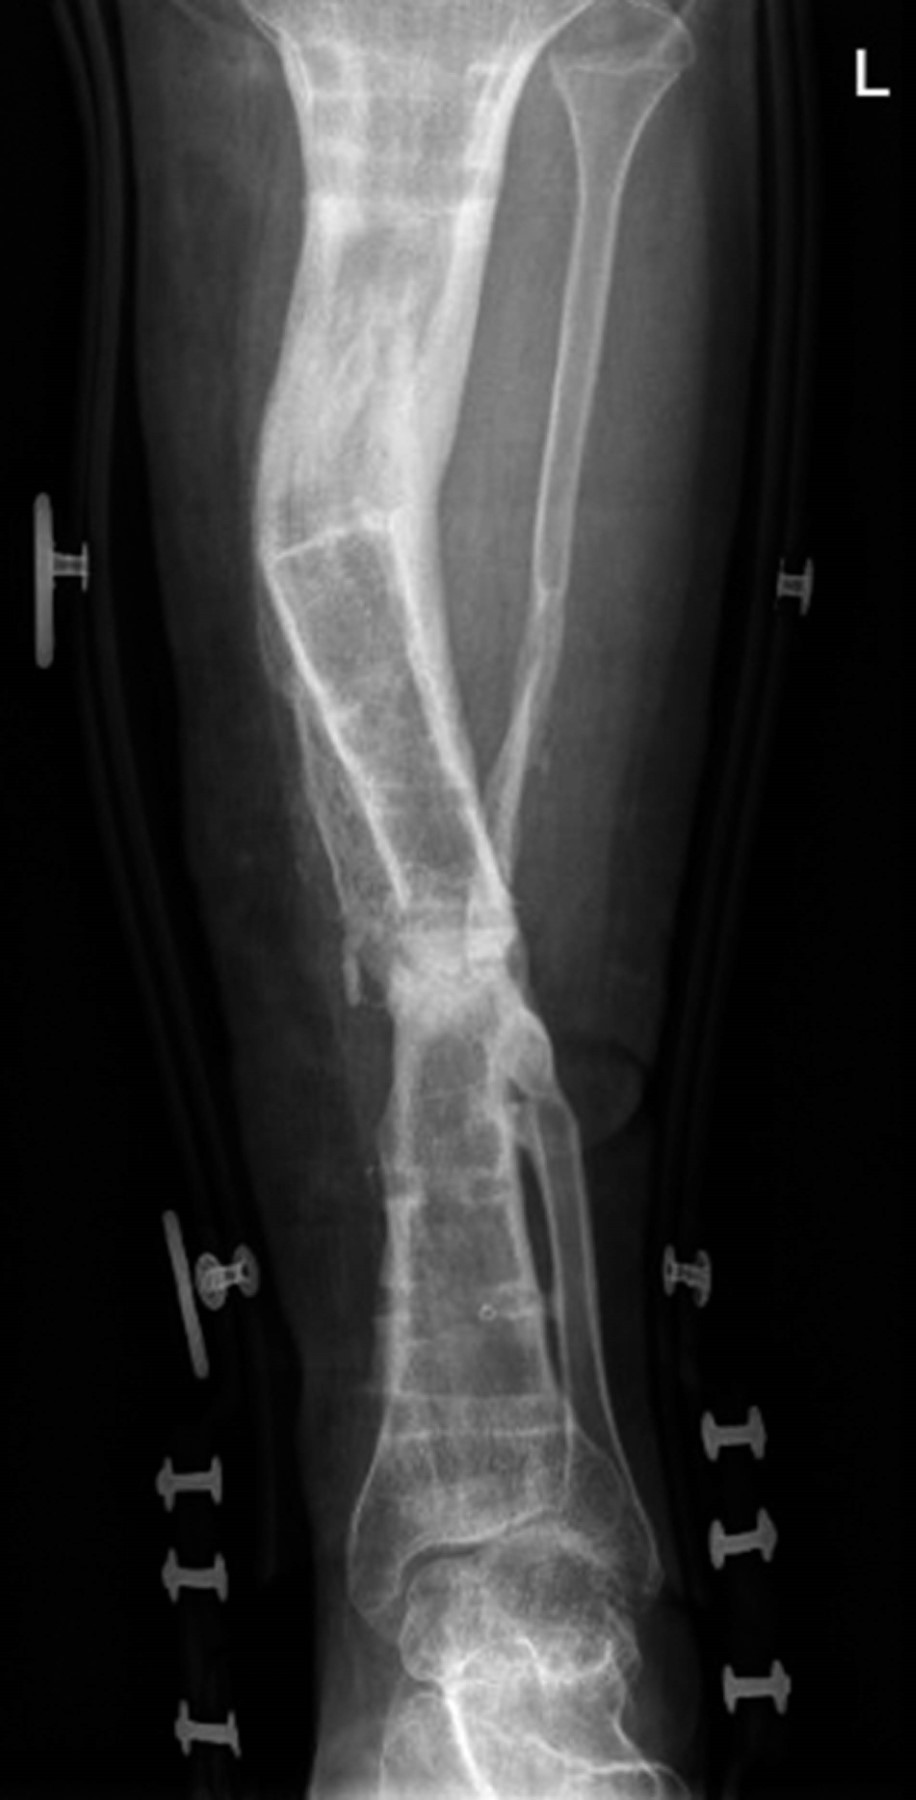

El método de De Bastiani consiste en la estabilización de los fragmentos comprometidos con tornillos troncocónicos no transfictivos, los cuales se fijan a un riel rígido con tres cabezales deslizantes (sistema de fijación externa tipo monorriel).2 Con el paciente en decúbito dorsal bajo bloqueo subaracnoideo en mesa radiolúcida y con intensificador de imágenes, se determinan líneas paralelas a la superficie articular, se colocan tres cabezales provisionales en regleta de elongador, se coloca un primer tornillo en cabezal proximal paralelo a articulación de rodilla, el segundo tornillo en cabezal distal paralelo a articulación de tobillo y un tercer tornillo en cabezal intermedio paralelo a la diáfisis de la tibia, después se colocan los tornillos restantes, quedando tres tornillos por cabezal, se cambian cabezales provisionales por los definitivos (Figura 3). Después se realiza incisión de 1 a 1.5 cm en la región proximal o distal según el sitio seleccionado para la corticotomía hasta periostio, se incide éste de manera longitudinal y se procede a perforar agujeros en las caras anteromedial y anterolateral del hueso para perforar la cortical posterior con broca 3.2 mm, mismos que se realizan con la menor distancia entre sí. A continuación, los agujeros se unen con un osteótomo una vez completada la osteotomía, porque la parte posterior se rompe de manera espontánea debido a la tensión aplicada antes del montaje. Se separan los segmentos mediante el distractor para asegurar que la osteotomía es completa y se confirma con el intensificador de imágenes. Se vuelven a aproximar los segmentos a distraer, sometiéndolos a una compresión leve y se aprietan las tuercas de bloqueo. Se cierra el periostio y la herida sin dejar drenajes. Se entrena al paciente y familiares sobre cómo realizar la distracción, cuándo iniciarla, frecuencia y sentido de la vuelta de la unidad de compresión-distracción, se le recomienda al paciente anotar en un cuaderno hora y fecha de distracción y sus observaciones como sensación de tracción, dolor o cualquier eventualidad. De no existir contraindicación alguna, se egresa al segundo día del postoperatorio. La fase de reposo dura en promedio 10 días. La distracción se realiza a razón de 1 mm por día, girando cuatro veces al día un cuarto de vuelta en sentido antihorario la unidad de compresión-distracción (0.25 mm cada 6 horas). Este promedio de distracción se acelera temporalmente cuando se observa una osificación rápida, o se reduce si la osificación es lenta o el paciente padece dolor o contractura muscular. La distracción es vigilada mediante controles radiográficos. Se cita a los 10 días del postoperatorio para valorar las heridas, retirar los puntos y verificar que entendió cómo iniciar la distracción. Tres citas semanales al inicio y quincenales posteriormente con radiografías de control. La fase de reposo dura en promedio un día. La distracción se realiza a razón de 1 mm por día, girando cuatro veces al día un cuarto de vuelta en sentido antihorario la unidad de compresión-distracción (0.25 mm cada 6 horas). Este promedio de distracción se acelera temporalmente cuando se observa una osificación rápida, o se reduce si la osificación es lenta o el paciente padece dolor o contractura muscular. La distracción es vigilada mediante controles radiográficos. Se cita a los 10 días del postoperatorio para valorar las heridas, retirar los puntos y verificar que entendió cómo iniciar la distracción. Nueva cita a los 10 días con radiografía de control para valorar que la distracción se realiza de manera correcta. Se le recomienda la carga parcial de aproximadamente 15 kg. Después se cita cada 30-40 días con radiografías de control para comprobar que se produzca la osteogénesis, en cuyo caso se continúa la transportación. Si la densidad del neoformado es pobre pero uniforme, se suspende la distracción por una o dos semanas. Si el neoformado es irregular, se comprime el segmento uno o dos centímetros a la misma velocidad de la distracción hasta que el callo sea uniforme, a continuación se reinicia la transportación. Al final de la transportación, cuando hay contacto de los dos fragmentos, la radiografía debe mostrar un callo uniforme (Figura 4). Se bloquea el cabezal del alargador para mantener el hueso nuevo en neutralización estable, el compresor-distractor es entonces retirado. Cuando así se requiere, una nueva cirugía puede realizarse para reavivar los bordes de la zona de contacto y colocar injerto para acortar el tiempo de consolidación, el soporte de carga en esta fase de neutralización se incrementa gradualmente en función del grado de mineralización del neoformado. Cuando la radiografía demuestra que el segmento es uniformemente denso y opaco, se dinamiza el elongador aflojando la tuerca del cabezal proximal y se bloquean las del cabezal medio y distal. Una vez que se ha logrado la corticalización completa, se procede al retiro del elongador y los tornillos troncocónicos, se realiza en quirófano y bajo anestesia general endovenosa (Figura 5).

De acuerdo con los criterios de selección, fueron incluidos un total de dos pacientes con pérdida ósea de tibia y fémur por pseudoartrosis infectada que recibieron tratamiento mediante transportación ósea con la técnica de De Bastiani durante el periodo de estudio. Uno fue del sexo masculino (50%) y uno femenino (50%). La edad promedio fue de 16 años (rango de 15 a 17 años). Una de las pérdidas óseas (50%) se presentaron como secuelas de fracturas expuestas y una de fracturas cerradas (50%). La fractura expuesta fue en la tibia izquierda y la cerrada en la tibia izquierda. Una de las fracturas se reportó por causa espontánea, idiopática, la fractura expuesta por caída de una caja de camioneta. En la fractura expuesta, el tratamiento inicial consistió en desbridamiento y fijación externa, con reducción abierta, fijación interna con placa de compresión bloqueable (LCP) 3.5. Para la fractura cerrada de tibia en reducción abierta fijación interna con placa LCP 3.5. Sólo un paciente no comenzó su tratamiento quirúrgico en este hospital (fractura cerrada de tibia) llegado a la consulta externa con placa fatigada y en pseudoartrosis infectada. La longitud de pérdida ósea promedio fue de 10 cm (rango de 7 a 11 cm). El sitio de la corticotomía en los dos casos fue diafisario proximal. La transportación ósea se inició en promedio con los 15 días después de la corticotomía (rango de 10 a 15 días). A los dos pacientes se les realizó técnica Masquelet durante el procedimiento. La velocidad de distracción promedio fue de 0.85 mm/día (rango de 0.57 a 0.98 mm/día). El tiempo de consolidación y corticalización del segmento transportado fue de 14.5 meses (rango de 6 a 22 meses), sólo en un caso fue de tres años (el caso de la fractura expuesta). El índice de corticalización promedio fue de 1.9 cm/mes (rango de 0.8 a 3.2 cm/mes). Los pacientes lograron la consolidación del segmento transportado aunque uno de los casos aún continúa con el fijador monorriel. Dos pacientes presentaron deformidad residual del segmento transportado, uno con retroverso de 6o y valgo de 5o; el segundo presentó anteverso de 15o. Discrepancia de las extremidades inferiores ocurrió en los dos pacientes, de 1.5, 2 cm y 2 cm. De acuerdo con el sistema de clasificación de Paley, dos pacientes tuvieron resultados óseos excelentes (71%) y uno buenos (29%) (Tabla 2).

Tal y como se realizó en el presente estudio, el inicio de la transportación ósea posterior a la corticotomía se recomienda entre los primeros siete a 15 días, ya que si se inicia en forma previa el neoformado no es de calidad adecuada y se fractura; después de 15 días la corticotomía consolida y es difícil iniciar la transportación. La velocidad de distracción recomendada es de ¼ vuelta al día, y el índice de corticalización reportado en la bibliografía es de 1 cm/mes en niños y de 2 a 3 cm/mes en adultos. Los resultados óseos y funcionales obtenidos en nuestro estudio son muy similares a los reportados por Paley y Tucker, quienes realizan este procedimiento. Una de las principales complicaciones encontradas durante la transportación ósea fue el proceso infeccioso, el cual estuvo siendo valorado por el Servicio de Infectología con antibioticoterapia basada en los cultivos. El dolor durante la transportación ósea es una complicación esperada secundaria a la distracción de los tejidos blandos, en esta evaluación, un paciente refirió dolor leve, el cual cedía a analgésicos orales; cuando la sintomatología no cede, es posible detener la distracción por un breve periodo, rehabilitar movilizando las articulaciones próximas y reiniciar posteriormente la distracción. Ningún caso presentó fractura durante el proceso; la fractura del neoformado es una de las complicaciones que pueden presentarse, según lo reportado por Aronson y Tucker.6 De acuerdo con nuestros resultados, consideramos que la transportación ósea es una buena alternativa en el manejo de las pérdidas óseas mayores de tibia, por lo que recomendamos su uso en casos de pérdidas importantes.7 Sin embargo, debe considerarse que durante el seguimiento pueden presentarse algunas complicaciones o dificultades técnicas, por lo que este procedimiento debe realizarse por cirujanos con un entrenamiento adecuado (Figura 6).

Figura 6